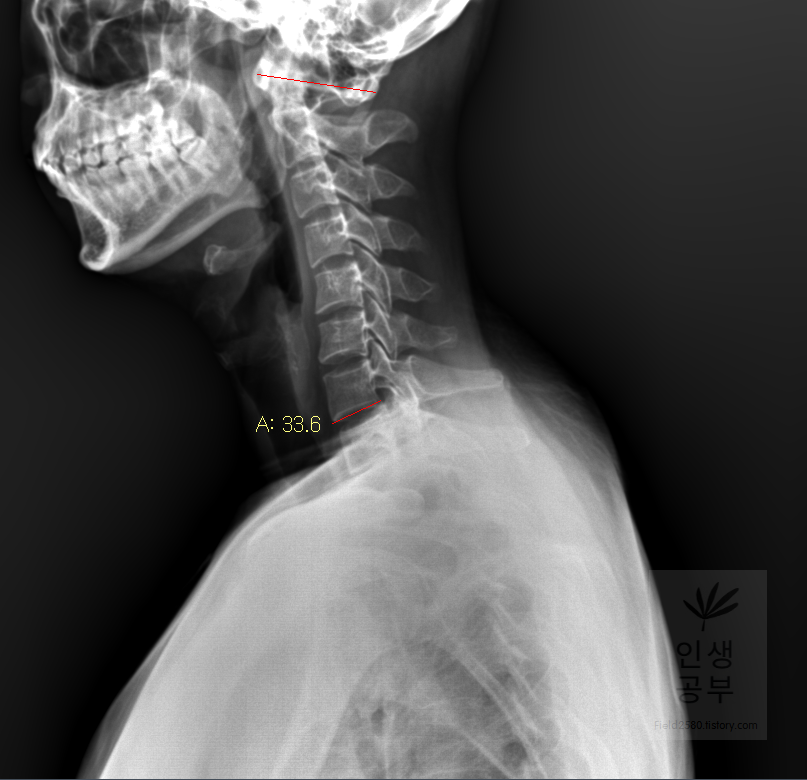

선 긋기를 이용해서 Cobb각을 그린다고 가정했을 때 측정하려고 하는 곳을 처음에 누르고 드래그로 쭉 끌어다주면 위와 같은 선이 생기고 선의 길이가 자동으로 측정됩니다. 첫 번째 목뼈(C1) 선을 그리기 위해 제일 튀어나온 앞쪽 부분 가운데 지점에(Center of Anterior arch) 점을 찍어줍니다. 후궁(Posterior arch) 제일 좁은 부위 가운데 지점에 점을 찍어줍니다. 두 점을 연결해주는 선을 그어줍니다. 이 선 이름을 고리 뼈 선(APL : Atlas Plane Line)이라고 합니다. 점은 조금 더 정확하기 위해서 하는 것이 찍어도 되고, 점을 찍지 않은 상태에서 선을 그으셔도 무방합니다.

일곱번째 목뼈 추체 밑면(Inferior endplate of C7)과 평행한 선을 그어줍니다.

위쪽 선을 따라서 선을 긋고 90도를 맞춰서 선을 그어줍니다. 동그라미 표시된 곳을 먼저 찍어주고, 화살표를 따라서 위쪽 선을 따라서 그려주고, 90도 방향에 맞춰서 아래로 그어줍니다. 노란색 글자와 숫자가 아래줄 맞춰 준 곳에 있는데 A는 Angle 각도이고 옆에 있는 숫자가 현재 긋고 있는 각도의 값입니다

아래 선을 따라서 선을 긋고 90도에 맞춰서 선을 그어줍니다. 동그라미 표시된 곳을 먼저 찍어주고, 화살표를 따라서 아래쪽 선을 따라서 그려주고 90도 방향에 맞춰서 위로 그어줍니다. 위쪽 선에서 그은 선과 교차되게 그어주시면 됩니다.

두 선이 교차된 곳에서 각도가 생기게 됩니다. 이 각도를 Cobb 각이라고 합니다. 위쪽에 각도를 재거나 아래쪽에 각도를 재어도 똑같으니 원하는 방향의 각도를 측정해 주시면 됩니다. 각도를 측정할 때에는 두선이 교차한 곳에 먼저 클릭해주고 위 화살표 방향대로 오른쪽 왼쪽의 교차한 선을 따라서 측정해 주시면 됩니다. 왼쪽선을 먼저 그어도 되고 오른쪽 선을 먼저 그어도 상관없습니다.

위쪽에 있는 선은 첫 번째 목뼈(C1) 선을 그리기 위해 제일 튀어나온 앞쪽 부분 가운데 지점에(Center of Anterior arch)에서 시작해서 후궁(Posterior arch) 제일 좁은 부위 가운데를 지나는 선이 되도록 이동해줍니다. 선 이름을 고리 뼈 선(APL : Atlas Plane Line)이라고 합니다. 점은 조금 더 정확하기 위해서 하는 것이 찍어도 되고, 점을 찍지 않은 상태에서 선을 그으셔도 무방합니다. 아래쪽에 있는 선은 일곱번째 목뼈 추체 밑면(Inferior endplate of C7)과 평행하게 선을 맞춰줍니다. 노란색 글자와 숫자가 아래줄 맞춰 준 곳에 있는데 A는 Angle 각도이고 옆에 있는 숫자가 Cobb 각입니다.